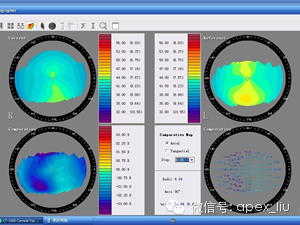

这是比较差异图,对不同的地形图计算叠加差异。可追踪圆锥的变化。纸质的地形图结果也无法演示。

这是同一眼地形图,左图中的角膜中央红色高曲率部分,实际上是角膜表面的分泌物,瞬目后再做地形图,角膜中央红色高曲率部分消失。

Placido盘镜面反射方法假设角膜的光轴和成像系统的光轴在一条直线上,它对光轴上的移位非常敏感 ,注视不良时,测量结果不准确。